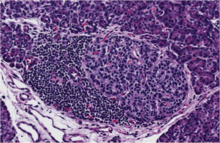

Type 1 diabetes (T1D) results from an autoimmune response against the insulin producing beta cells of the pancreas.

This destruction of beta cells causes patients to develop a lifelong dependence on insulin replacement therapy. Unfortunately, insulin injections are often insufficient for preventing many severe complications including heart disease, kidney failure, and blindness, among others. The disease process that leads to the development of T1D has been under investigation for more than 100 years. Several of the major players have been identified, but many key mechanisms of disease development remain undiscovered.[3]

The majority of studies investigating type 1 diabetes have been performed in rodents due to the lack of availability of human tissues. While these studies have allowed us to identify potential causes for T1D and have directed many researchers in the development of their methods, key biological differences between rodents and humans prevent their use to uncover the specifics of disease progression.[4] nPOD grew out of a vision to bridge this gap of understanding by creating a biobank to collect and distribute diabetes-associated human tissues to researchers.